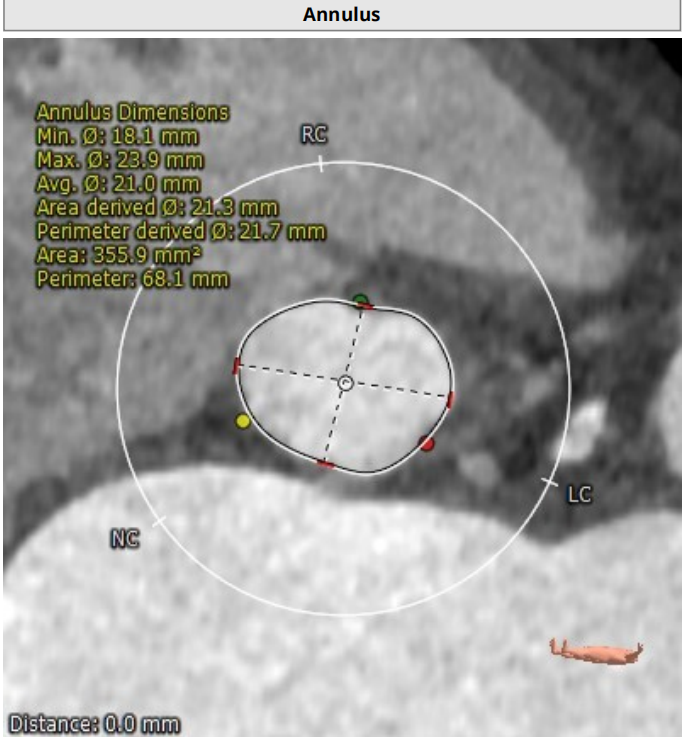

瓣环

周长:68.1mm 平均直径:21.7mm

法氏窦

直径:25.3*24.2*25.1mm

窦管结合部

平均直径:25.8mm

升主动脉

平均直径:31.9mm

左冠高度高度:14.6mm

右冠高度高度:9.8mm

主动脉瓣角度 44°

钙化积分68mm³